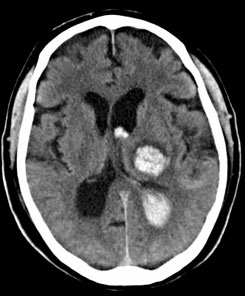

Tomografía computarizada Cerebral

< Volver a "Tomografía Computarizada (TC) con Inteligencia artificial"Se utiliza para el estudio de las diferentes estructuras cerebrales y sus patologías. Es especialmente útil para el diagnostico de hemorragias intracerebrales y es la opción de diagnóstico cuando está contraindicada la resonancia magnética.